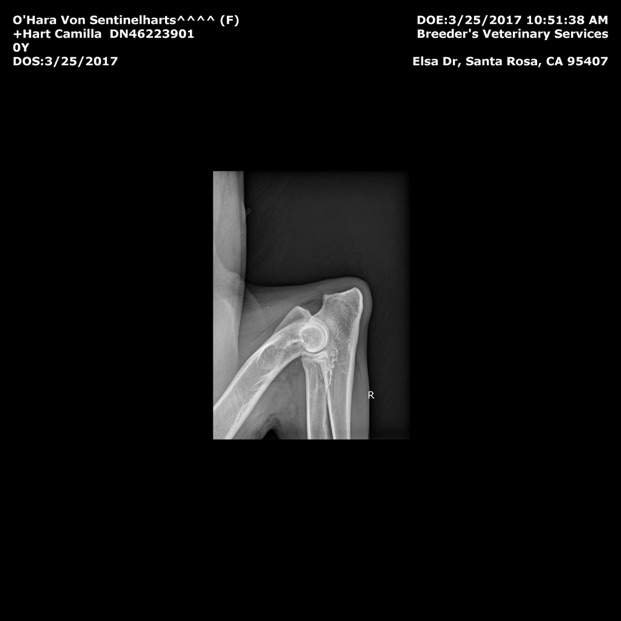

Hips- OFA GOOD GS-99766G24F-VPI

Elbows- OFA Normal  GS-EL38352F24-VPI